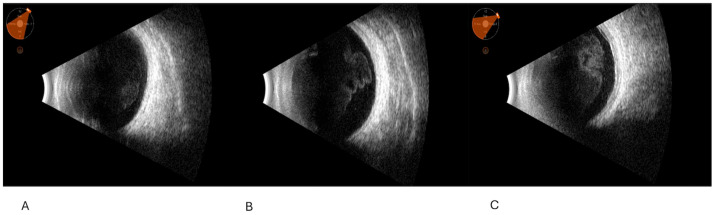

背景和目的:葡萄膜炎掩盖综合征或假面综合征(UMSs)是一组眼部疾病,有几种系统性的潜在原因,恶性或非恶性,模仿葡萄膜的炎症状态。它们通常难以用眼科检查等传统技术检测和诊断。眼部B(二维)超声(OBU)是一种无创、可重复、快速的超声方法,对导致全身性疾病的间接征象有效。其有效性与其他成像工具相当。多发性硬化的病因往往很严重,因此早期诊断和及时治疗至关重要。本研究旨在确定这些形式的超声征象,这可以帮助医生发现潜在的UMS原因。材料和方法:这是一项连续、回顾性、非随机的研究。该研究于2022年1月至2024年12月在意大利巴里大学医院综合诊所进行。共纳入186例患者,年龄从10岁到85岁不等。所有患者均行b超检查(Quantel Medical ABSolu Ocular Ultrasound)。结果:所有患者均报告视力模糊,并伴有视力下降(结论:准确诊断UMS相当具有挑战性,许多不同类型的UMS经常未被发现。这种识别的复杂性往往导致诊断不足,这意味着提高对这种疾病的认识和理解是必不可少的,以便更好地识别和治疗。及早发现这些形式是必要的。OBU的使用可以帮助早期诊断这些形式的间接迹象并及时治疗。它与其他诊断成像技术(如核磁共振成像)相比要好,但这并不意味着它取代了它们;它可以为多模态成像提供附加价值。

Background and Objectives: Uveitis-masked syndromes or masquerade syndromes (UMSs) are a group of ocular conditions with several systemic underlying causes, malignant or nonmalignant, that mimic the inflammatory status of the uvea. They are often difficult to detect and diagnose with traditional techniques, such as ophthalmic exams. Ocular B (bidimensional)-ultrasound (OBU) is a non-invasive, repeatable, rapid ultrasound method effective in indirect signs that lead back to systemic diseases. It is comparable in effectiveness with other imaging tools. The cause of UMSs can often be serious, and therefore early diagnosis and prompt treatment are critical. This study aimed to identify the sonographic signs of these forms, which can help physicians discover the cause underlying UMS. Materials and Methods: This was a consecutive, retrospective, nonrandomized study. This study was conducted at the University Hospital Polyclinic of Bari, Italy, from January 2022 to December 2024. A total of 186 patients were included, from 10 to 85 years old. They all underwent B-scan ultrasonography (Quantel Medical ABSolu Ocular Ultrasound). Results: All patients reported blurred vision, which could be accompanied by visual reduction (<20/40, Snellen charts), photophobia, floaters, flashes, proptosis, and redness. In all cases, we noted peculiar ultrasonographic signs, which allowed us to discriminate the underlying systemic diagnosis, such as vitreous corpuscles, choroid thickening, and primitive or metastatic solid tumors. Finally, we identified different diseases, such as primary intraocular lymphoma (PIOL), other lymphoproliferative conditions, orbital plasmacytoma, uveal melanoma, metastasis, endogenous endophthalmitis, retinal detachment, central serous retinopathy, metallic foreign bodies, ocular amyloidosis, and drug-induced UMSs. The sensitivity and specificity of ocular ultrasound compared to multimodal ocular imaging in UMSs were as follows: for primary intraocular lymphoma (PIOL) and other lymphoproliferative conditions, 0.98 (95% CI, 0.80-1) and 0.68 (90% CI, 0.40-0.92), respectively; for orbital plasmacytoma, 0.64 (92% CI, 0.52-0.86) and 0.66 (93% CI, 0.48-0.89), respectively; uveal melanoma, 1.00 (98% CI, 0.88-1.00) and 0.98 (95% CI, 0.86-0.98), respectively; metastasis, 0.75 (95% CI, 0.53-0.85) and 0.85 (95% CI, 0.48-0.98), respectively; endogenous endophthalmitis, 1.00 (95% CI, 0.50-1.00) and 0.83 (95% CI, 0.48-0.98), respectively; retinal detachment, both were 1.00 (95% CI, 0.87-1.00 and 0.84-0.97, respectively); central serous retinopathy, 0.60 (80% CI, 0.41-0.88) and 0.85 (95% CI, 0.52-0.98), respectively; metallic foreign bodies, 1.00 (95% CI, 0.78-1.00) and 0.99 (95% CI, 0.99-1.00), respectively; ocular amyloidosis, 0.77 (82% CI, 0.52-0.90) and 0.83 (80% CI, 0.49-0.88), respectively; and drug-induced UMSs, 0.64 (95% CI, 0.49-0.88) and 0.85 (95% CI, 0.52-0.98), respectively. Conclusions: Diagnosing UMS accurately can be quite challenging, and many of its different types frequently go undetected. This complexity in identification often leads to underdiagnosis, meaning it is essential to improve awareness and understanding of the condition in order to achieve better recognition and treatment. Early detection of these forms is imperative. The use of OBU can help diagnose indirect signs of these forms early and treat them promptly. It compares well with other diagnostic imaging techniques, such as MRI, but this does not mean that it replaces them; it can offer added value in multimodal imaging.